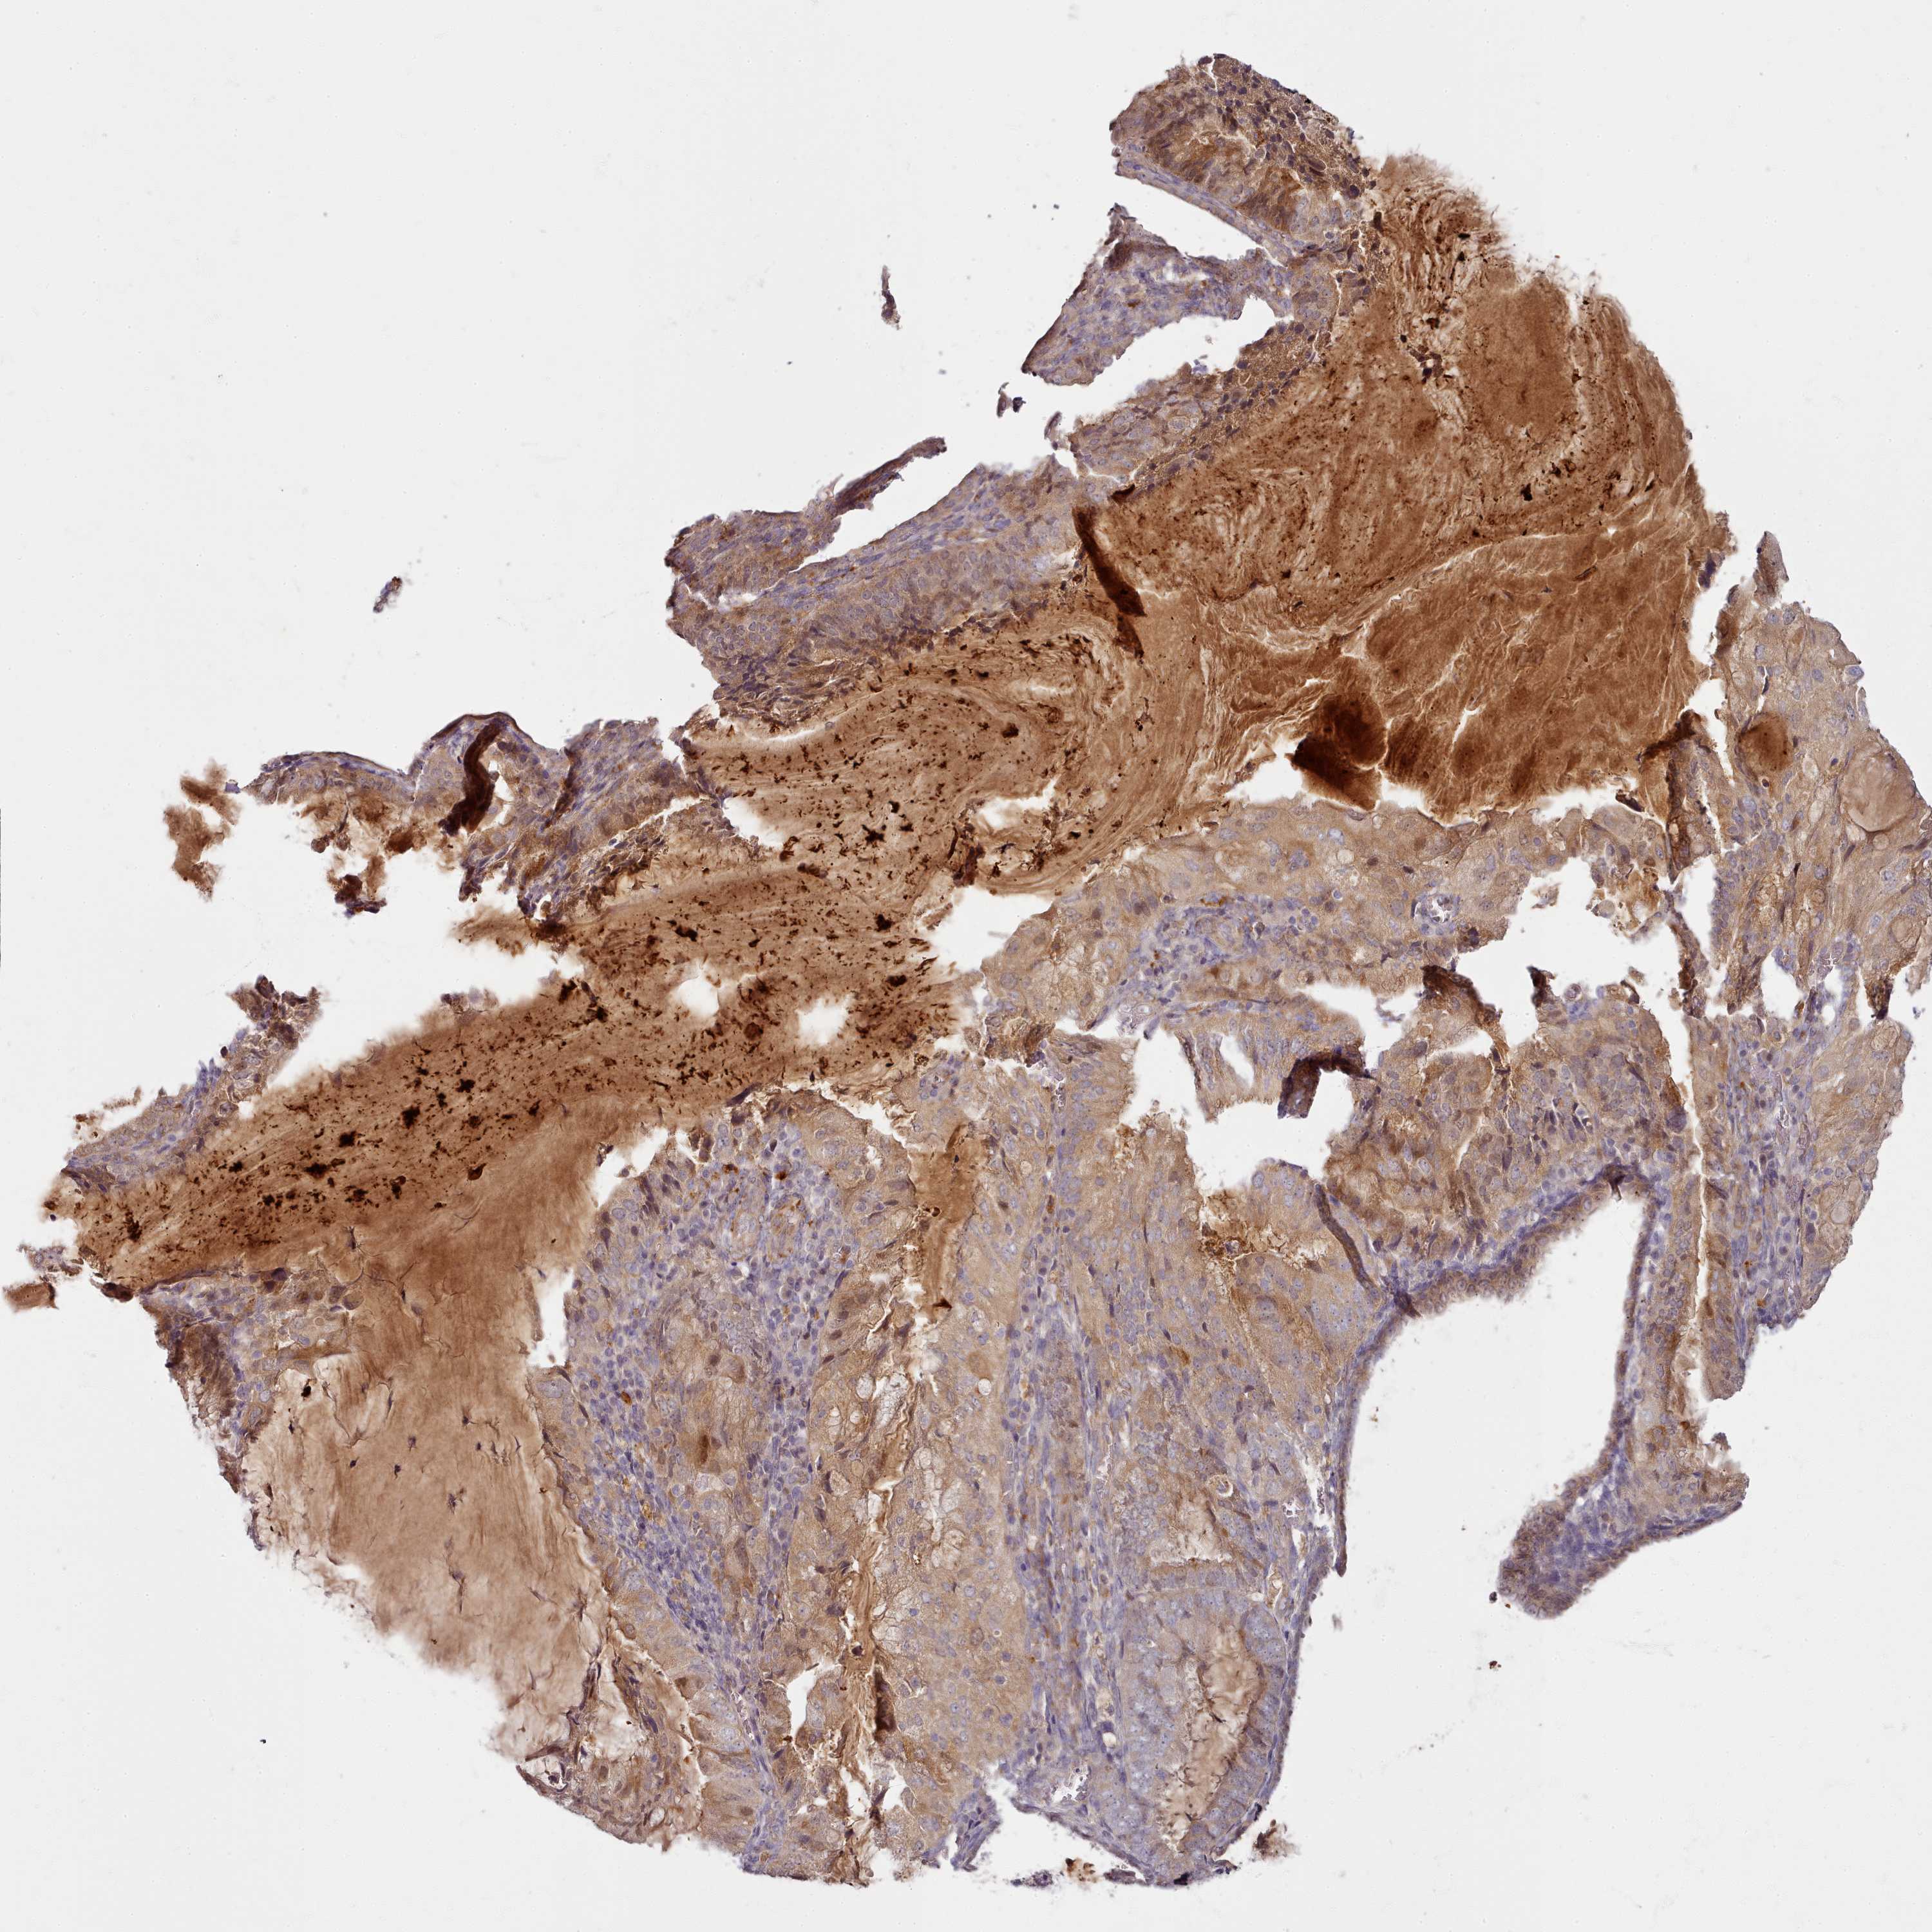

ENDOMETRIAL CANCER - Protein expressioni

A mouse-over function shows sample information and annotation data. Click on an image to view it in a full screen mode. Samples can be filtered based on level of antibody staining by selecting one or several of the following categories: high, medium, low and not detected. The assay and annotation is described here.

Note that samples used for immunohistochemistry by the Human Protein Atlas do not correspond to samples in the TCGA dataset.

Antibody stainingi

Antibody staining in the annotated cell types in the current human tissue is reported as not detected, low, medium, or high, based on conventional immunohistochemistry profiling in selected tissues. This score is based on the combination of the staining intensity and fraction of stained cells.

Each image is clickable and will lead to virtual microscopy that enables deeper exploration of all samples and also displays staining intensity scores, fraction scores and subcellular localization as well as patient and tissue information for each sample.

Antibody HPA038604

Antibody CAB025607

Staining

High

Medium

Low

Not detected

Intensity

Strong

Moderate

Weak

Negative

Quantity

>75%

75%-25%

<25%

None

Location

Nuclear

Cytoplasmic/membranous

Cytoplasmic/membranous,nuclear

Adenocarcinoma, NOS

Adenocarcinoma, metastatic, NOS